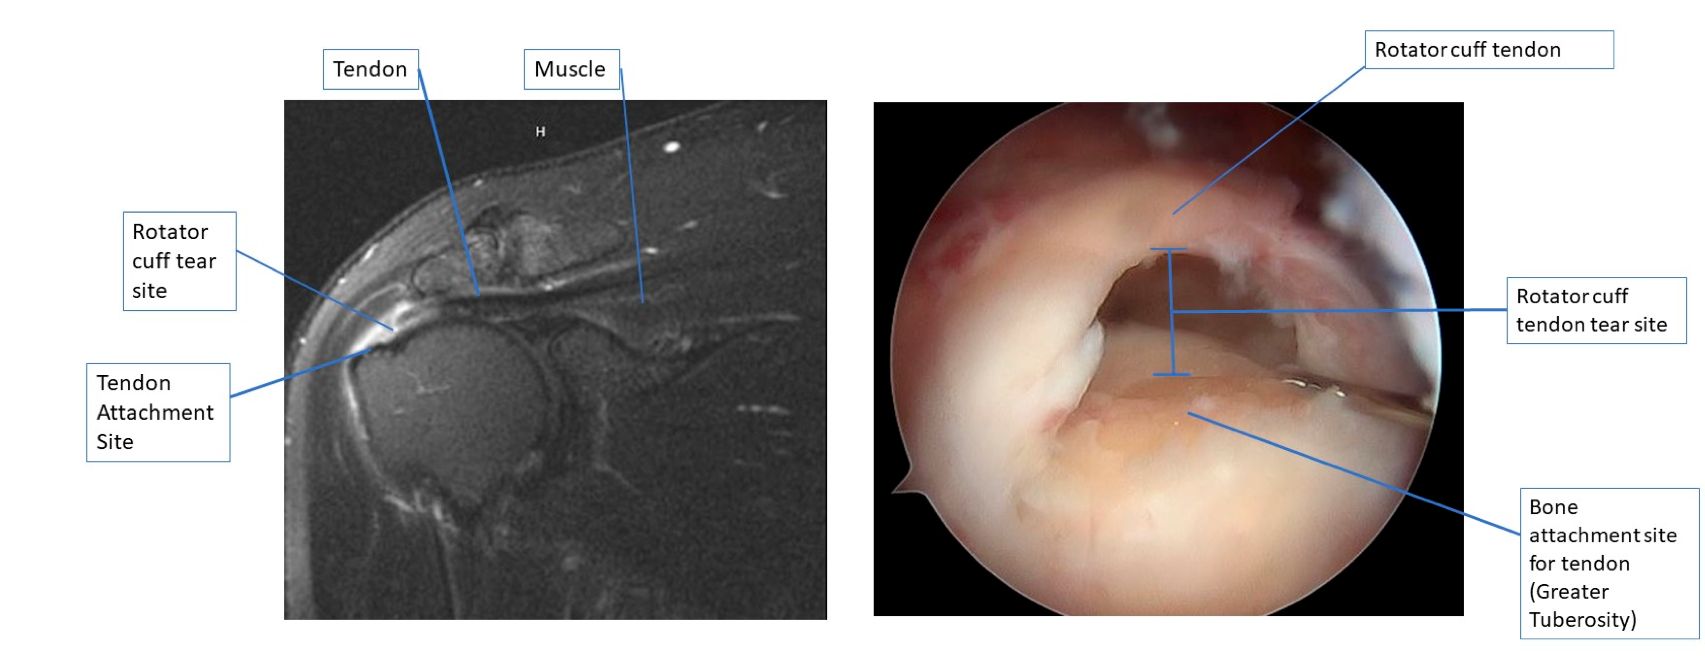

MRI images of a full thickness rotator cuff tear.

Arthroscopic images of a partial bursal sided rotator cuff tear.